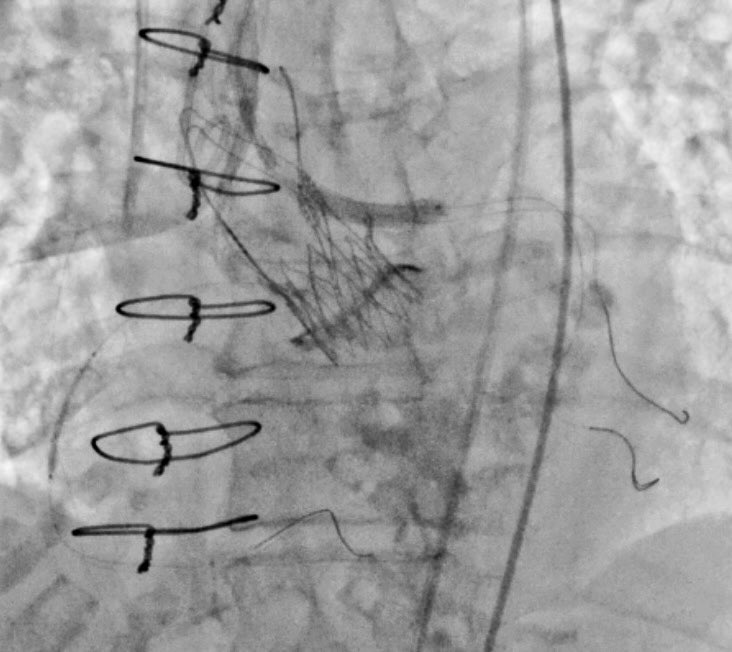

Mitroflow 21 valve-in-valve TAVI with Acurate Neo S. - Coronary protection x 2. - Cracking with Atlas gold 20mm >>>mean gradient 6mmHg vs 30mmHg. - Left Main PCI with ‘chimney technique’ pierredeharo DrThomasCuisset AP-HM - Hôpitaux Universitaires de Marseille

Mitroflow 21 valve-in-valve TAVI with Acurate Neo S.

- Coronary protection x 2.

- Cracking with Atlas gold 20mm  >>>mean gradient 6mmHg vs 30mmHg.

- Left Main PCI with ‘chimney technique’